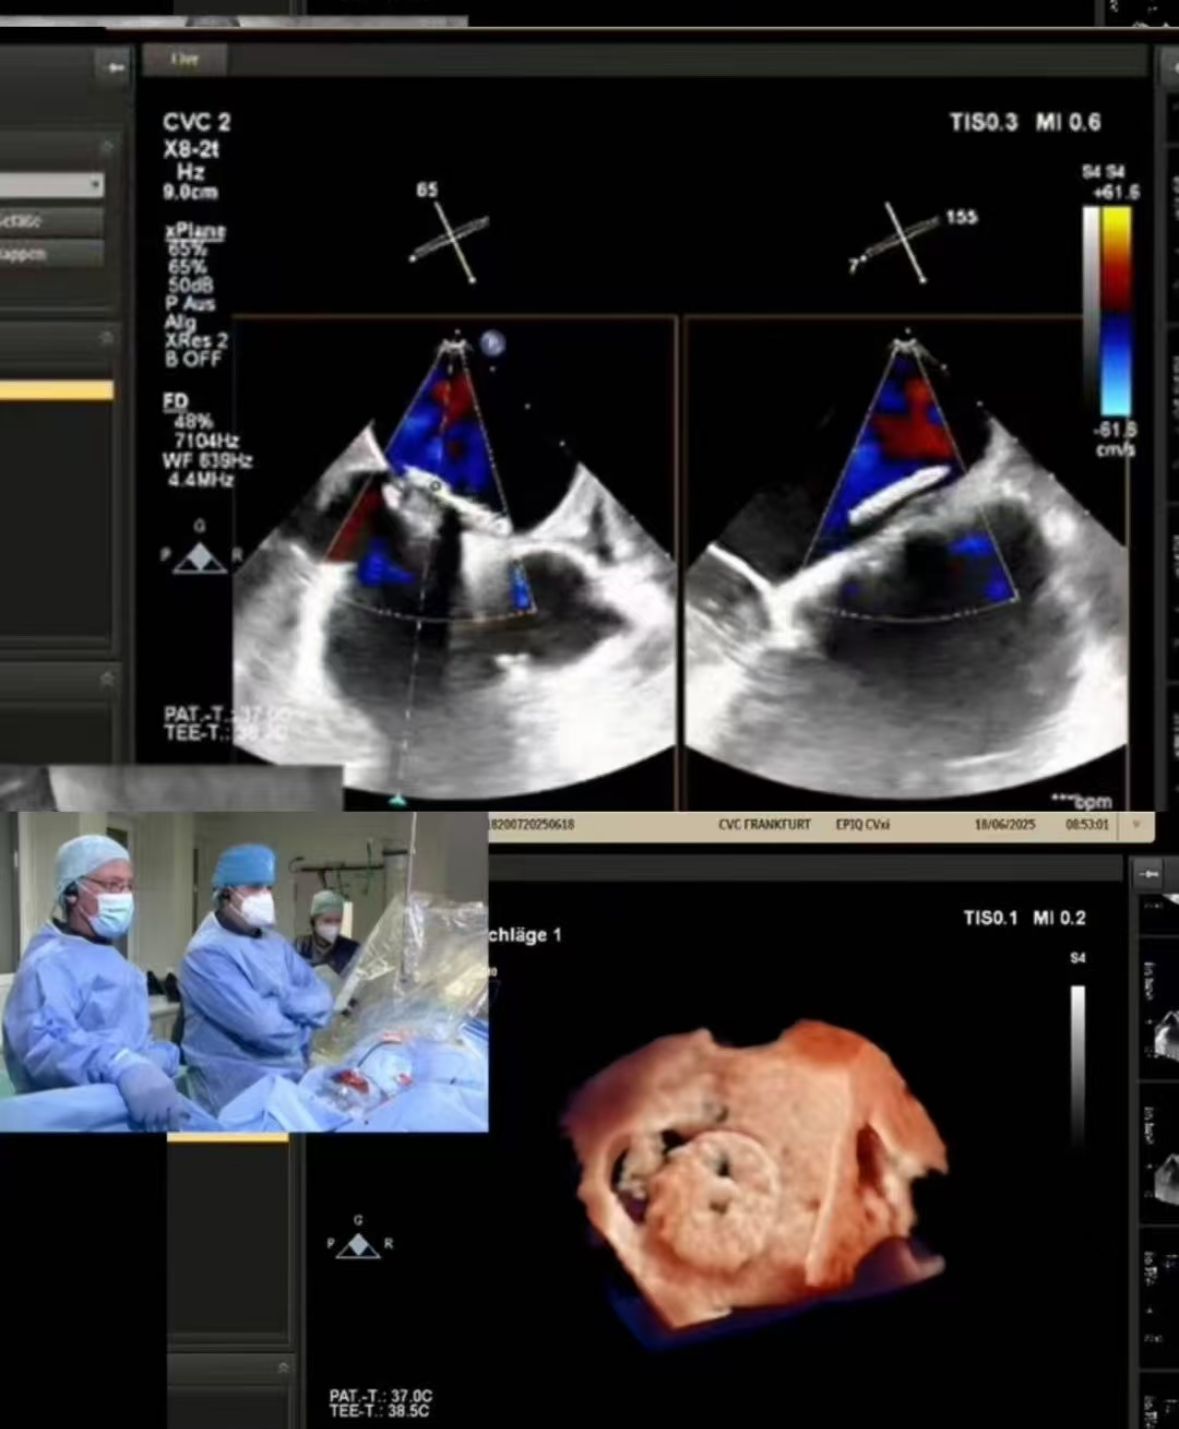

Thrilled to showcase our MemoSorb PFO Occluder – the world's first absorbable device (degrades to water & CO₂ within 1 year) – during a live broadcast from the Blue Room at CSI Frankfurt!

Kami menjalankan penutupan PFO yang kompleks dilakukan di CVC Frankfurt pada pasien wanita berusia 60 tahun dengan:

1. Stroke embolik berulang (2014, 2021)

2. Alergi nikel parah (indikasi untuk perangkat logam)

3. Sisa shunt setelah penutupan sebelumnya

2. Penutupan yang tepat: Pencitraan Waktu Nyata dipandu penyebaran sempurna dalam anatomi yang menantang (PFO terowongan fenestration).